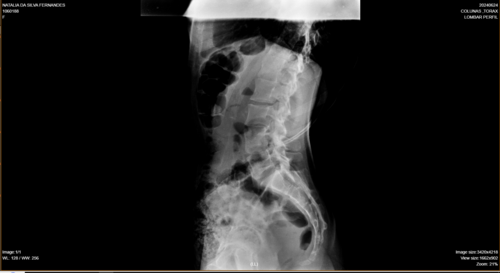

Olá, me chamo Natália da Silva Fernandes, tenho 21 anos, moro na cidade de Ji-Paraná, no estado de Rondônia. Fui diagnosticada com escoliose e venho na busca de um tratamento pelo SUS há um tempo, mas não obtive retorno até o presente momento. Passei por algumas consultas com ortopedistas do SUS, peguei encaminhamentos para passar com um neorocirurgiao e depois de um longo período de espera, consegui uma consulta com um neorocirurgiao do SUS, quando ele viu meu estado de saúde ele disse q a única solução é fazer a cirurgia, como na cidade não tem estrutura para realizar a cirurgia através do SUS, peguei mais um encaminhamento para consultar pela segunda vez por outro neurocirugiao, mas na cidade de Porto Velho, e nisso fiquei no aguardo desse agendamento mas até o momento nenhum retorno do SUS, ou seja, nenhum pedido de agendamento de cirurgia, apenas consultas, é um processo burocrático conseguir uma cirurgia pelo SUS, pois tem uma lista de pacientes na espera por vaga. Devido à demora do SUS , recorri a um neurocirurgião particular e o diagnóstico que recebi foi o mesmo, necessito fazer a cirurgia com urgência.Atualmente, me encontro num quadro doloroso, minha escoliose está com 86° de encurvatura, sinto dores constantes, tenho dificuldade em andar e às vezes dificuldade em respirar, porque são dores muito fortes. Para dormir, é uma luta constante para achar uma posição que dê menos desconforto . Diante de todo esse processo doloroso, e todo o tempo que venho recorrendo ao SUS e não obtendo uma solução favorável, a preocupação aumenta cada dia, pois não tenho condições de custear nem a cirurgia, nem o tratamento pós-cirúrgico. Foi então que surgiu a solução de fazer a vaquinha. A cirurgia fica em média de 250 mil reais com o tratamento pós-cirúrgico. Deixo na descrição os laudos e exames que venho realizando como transparência da minha situação.Toda ajuda é bem-vinda!Ajude-me compartilhando em suas redes sociais. Deixarei minha rede social para entrarem em contato comigo para mais informações: @_fe3_n47ou acesse o link abaixo e vá direto ao meu perfil.https://www.instagram.com/_fe3_n47?igsh=MXA1bDEzNW53YzZ5NA==